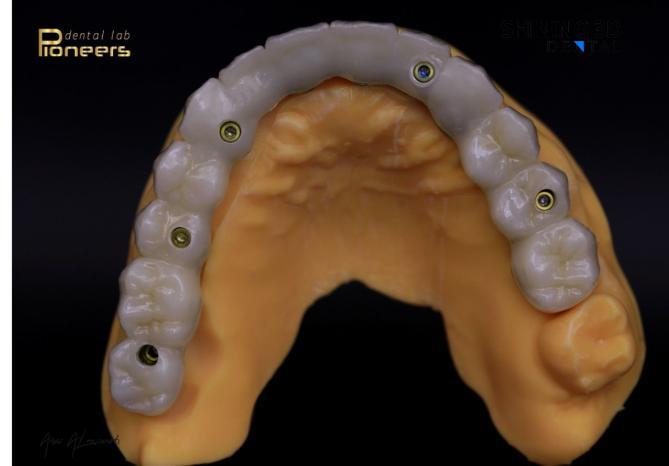

Final prosthesis

After the patient had adapted to the provisional restorations, with healthy gingival recovery and successful osseointegration, the final prosthesis was fabricated using a milling machine. The try-in was first performed extraorally on a physical model to confirm passive fit, evaluate occlusion, and assess tooth morphology.

Fig. 27–32: Final prosthesis